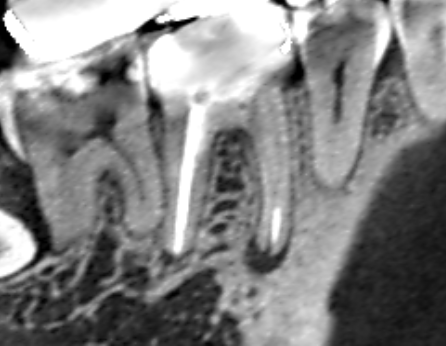

ブリッジの支台になっている上顎側切歯に大きな膿がみられ、この歯を残せなければ無傷の隣の犬歯を削ってブリッジの支台にしなければいけないケースです。できれば、上顎側切歯の膿を治して再度ブリッジの支台として使いたいので、精密再根管治療を行うことになりました。 上顎側切歯の冠状断のCT画像です。 側切歯の根…